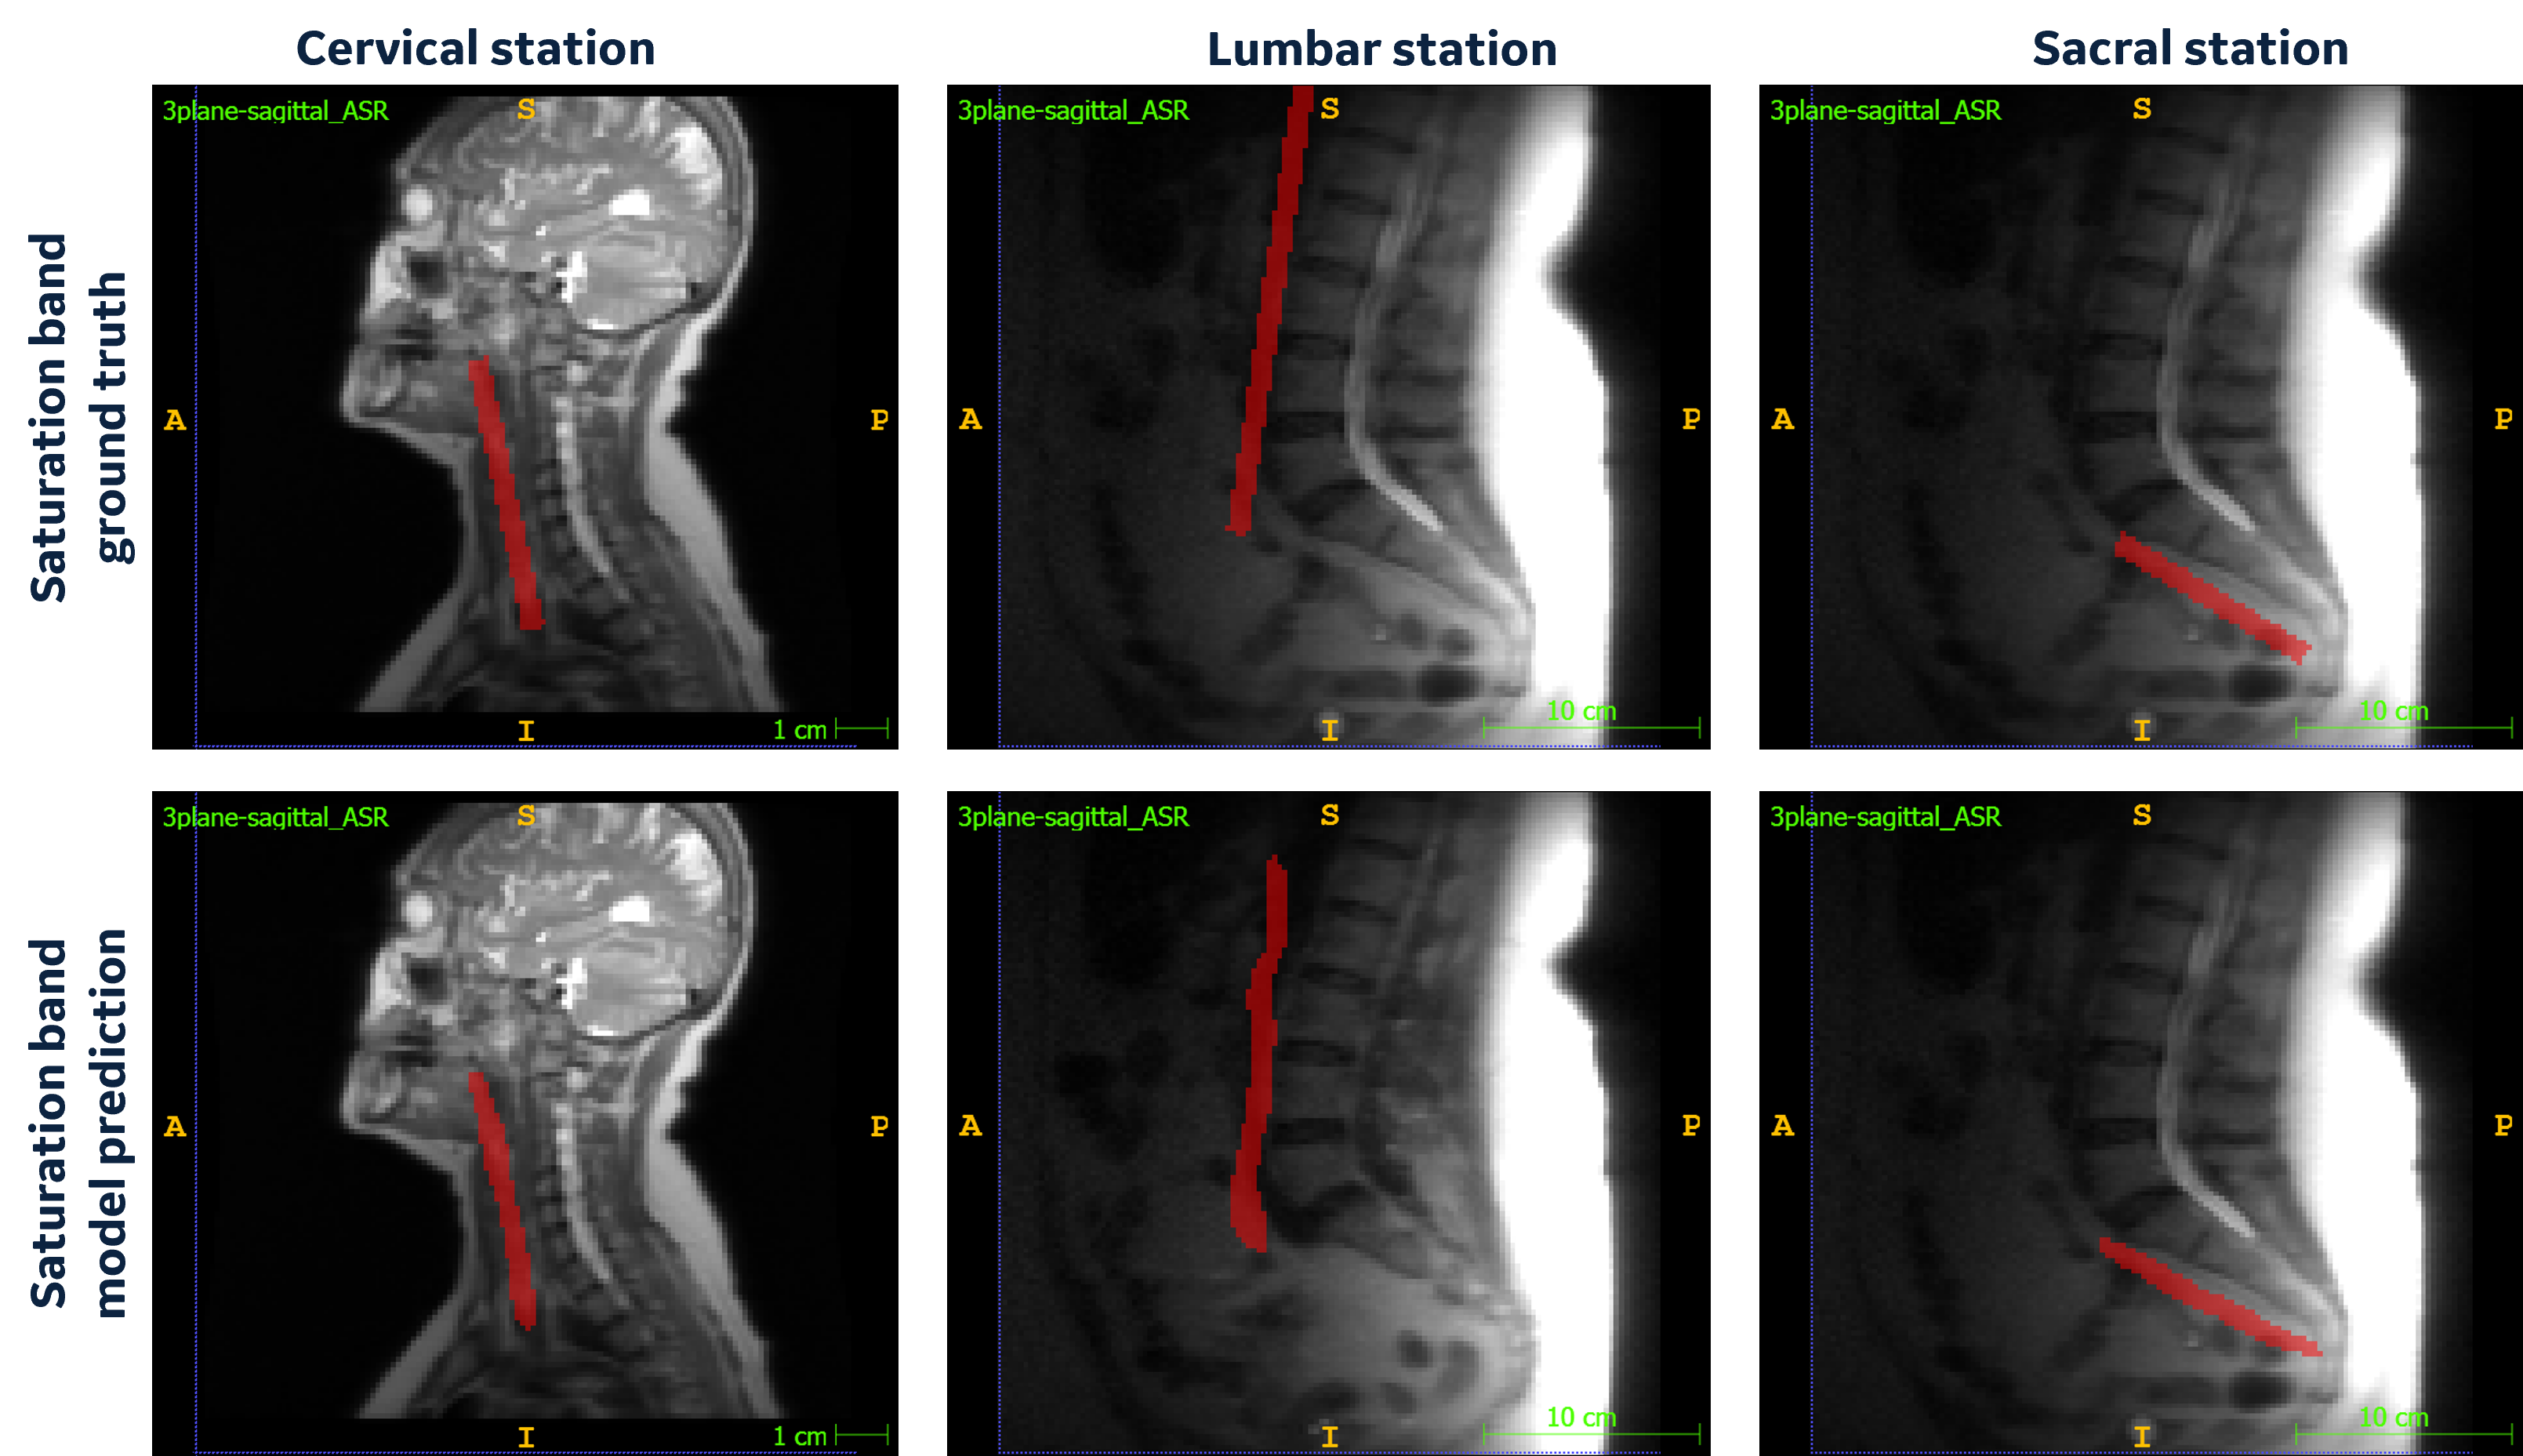

Our DL model learns the spine anatomical structure for SB placement. Figure 2 shows the results of model predictions at cervical, lumbar, and sacral stations. The predicted voxels will be used to fit a plane that will give the DL-estimated plane for SB placement in the localizer images. Although the mean dice score of these segmentations is low (Figure 3a), other relevant metrics strongly support the high accuracy of the model predictions. The MAD error and center for DL model prediction at all the spine stations were found to be lower than 3 mm (Figure 3b). There are few cases with outliers or error value of more than 3mm observed. However, given the value of MD_V was found to be greater than 0 in all the cases, it can be established that the SB plane predicted by the DL model doesn’t intersect with the respective spine station vertebrae (Figure 3c).

Figure 2: Cervical, Lumbar and Sacral localizer images with ground truth saturation band and model predicted saturation band voxels.